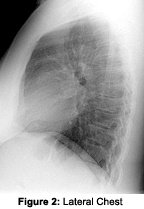

The routine chest study includes the following: PA chest and lateral chest views. The PA chest view is taken with a non-grid technique, using a 14 x 17 cassette at 72" film focal distance at a kVp of 100 to 110, with a time of 1/10 of a second or less. Collimation is a little less than the film size. One must be careful to include the apices of the lungs and the lateral-most margins of the thorax and costal-phenic recesses. Most patients can be accommodated by a 14 x 17 cassette. X-ray is taken on inspiration.